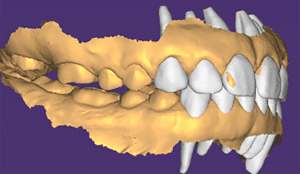

Mme AB vient en consultation pour deux raisons. La première est une douleur intense à chaque fois qu’elle boit ou mange froid. La deuxième est l’apparence de son sourire. Elle trouve que ses dents ont « raccourci » et qu’elles « s’effritent ». C’est devenu un complexe handicapant. À L’examen clinique on observe (Fig.1a, b, c, d, e) une usure vestibulaire de toutes les dents : plus prononcée au maxillaire et assez légère sur les incisives mandibulaires, une classe III canine et molaire droite, une classe I canine et molaire gauche avec une légère déviation des milieux et une usure importante des faces palatines du bloc IC maxillaire ainsi que des faces occlusales de 16 et 26. On constate aussi que les faces occlusales des autres dents sont moins touchées en apparence. On observe que les amalgames de 36 et 48 sont en relief par rapport à la dent support. Il est raisonnable de supposer qu’à l’origine ils devaient obturer une cavité et donc être à l’intérieur de la dent. Ceci témoigne donc aussi d’une forte usure sur 36 et 46. On observe enfin que les courbes de Spee sont complètement plates.

Fig.1a, b, c, d, e : Examen clinique.

Fig.1b.

Fig.1c.

Fig.1d.

Fig.1e.